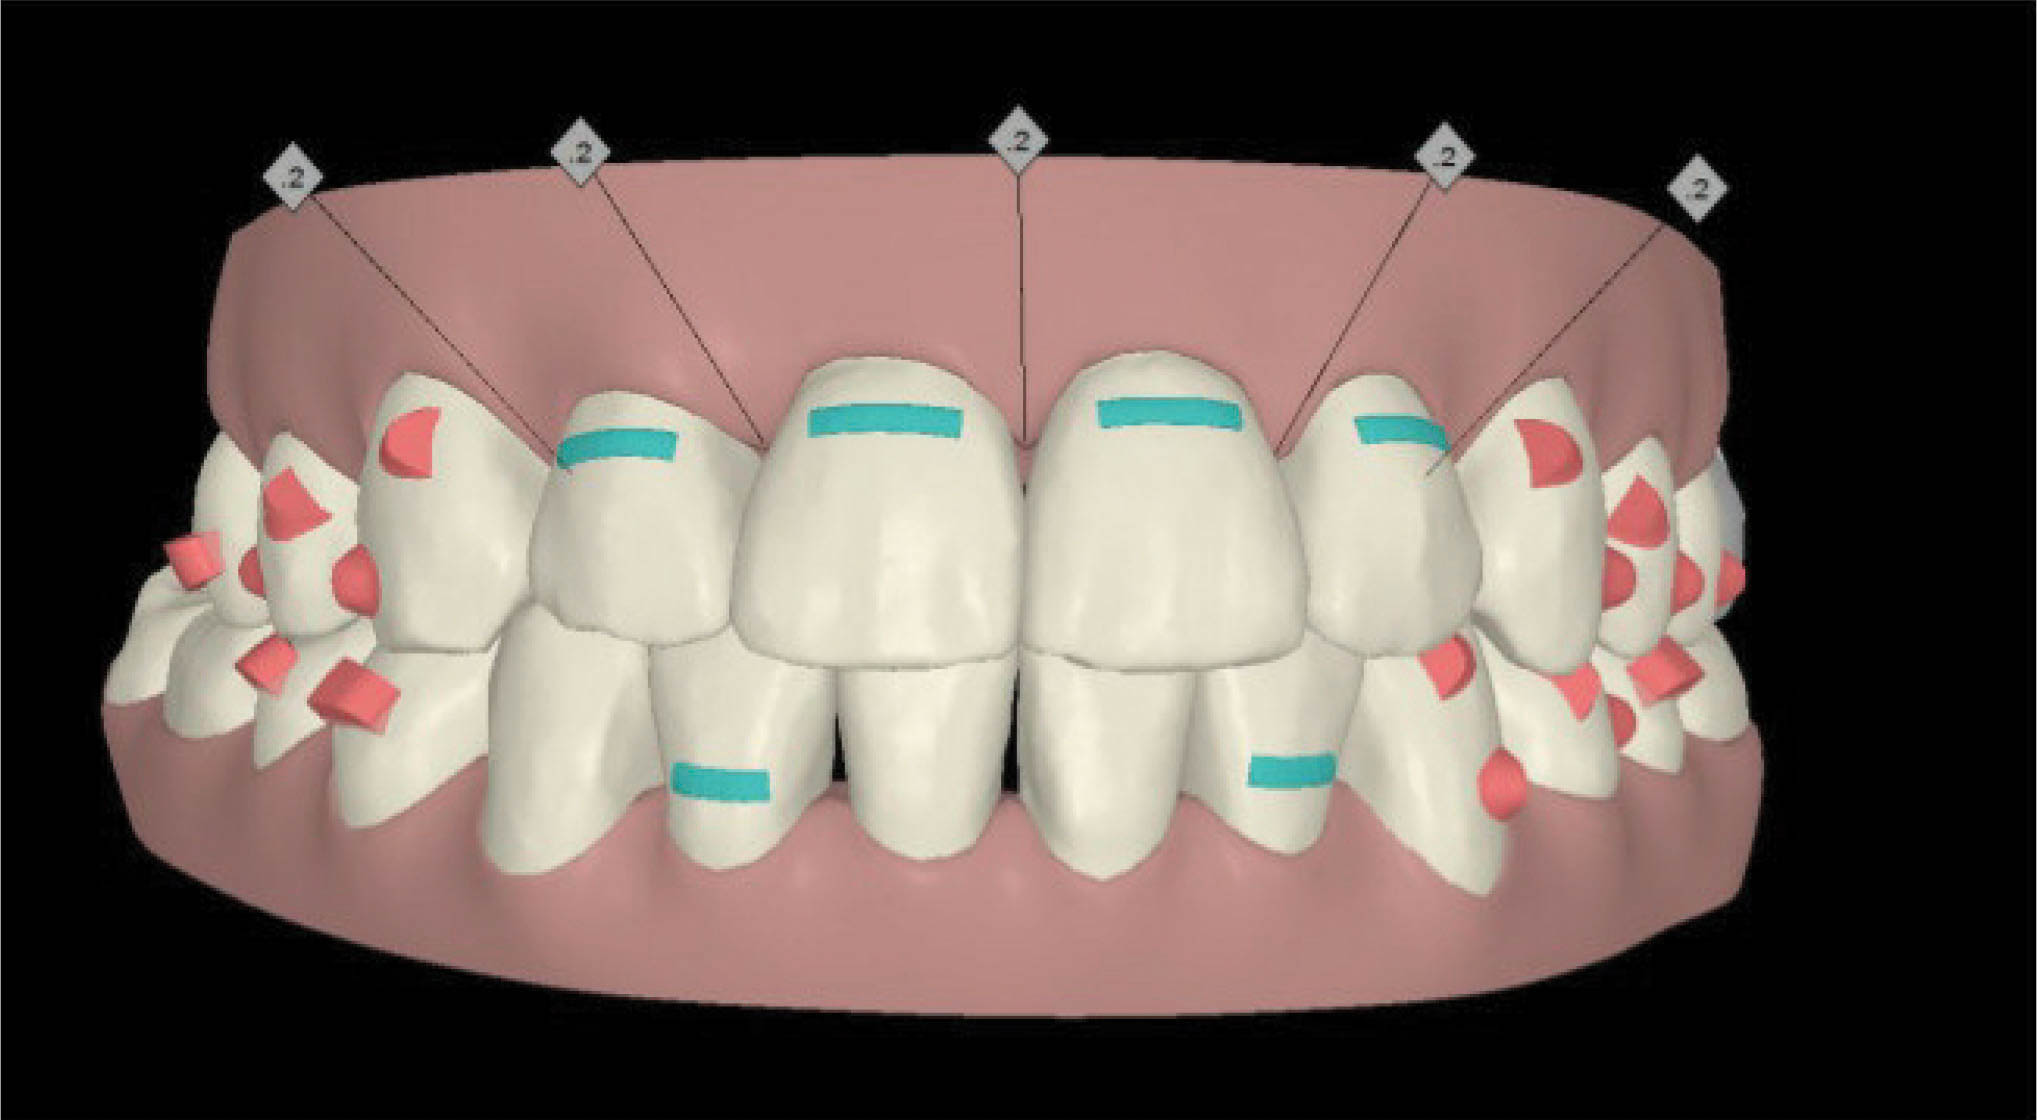

در طرح درمان کامپیوتری (شکل 153-6) استریپ بالا انجام گرفت تا با عقب کشیدن انسیزورها به ظاهر زیباتری برسیم. نتیجه درمان در شکل 154-6 مشخص است.

شکل153-6

شکل154-6